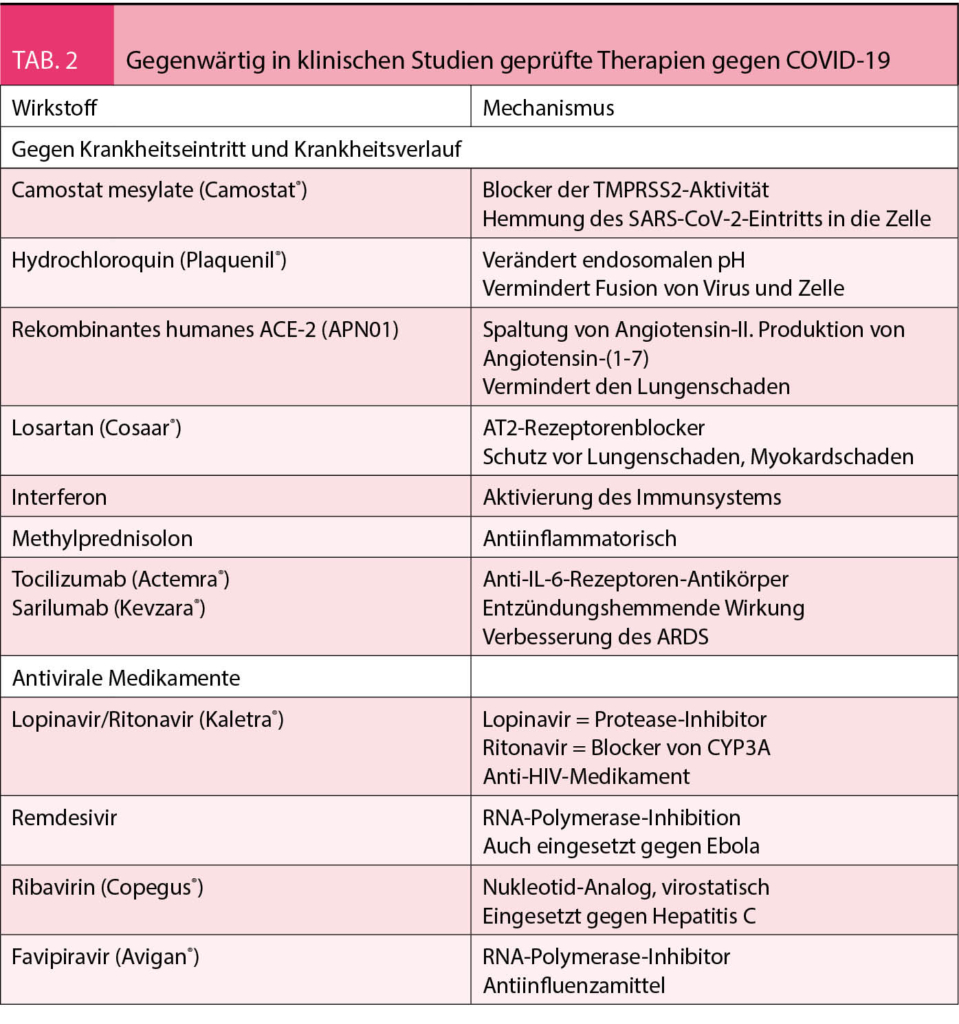

Es wird angenommen, dass die Übertragung vorwiegend über Tröpfchen des Atemsystems erfolgt, ähnlich wie bei der Influenza (4). Die Inkubationszeit variiert zwischen 2-14 Tagen. Angesteckte Individuen bleiben infektiös, d. h. können die Krankheit zwischen acht bis 37 Tage übertragen. Bei über 90% der Infizierten können aber 10 Tage nach Ausbruch der Symptome keine Viren mehr nachgewiesen werden. Wie allgemein bekannt, variiert die Klinik der Krankheit stark und die Schwere der Krankheit ist altersabhängig. Ein unbekannter, vielleicht beträchtlicher Teil der angesteckten Personen kann asymptomatisch bleiben. Interessanterweise finden sich aber auch bei asymptomatischen Patienten in 50% in einer CT-Untersuchung der Lunge die Zeichen der Infektion mit typischen retikulären Zeichen und Verschattungen. Die klinischen Symptome sind in der Tabelle 1 zusammengefasst. Die Krankheit beginnt meist mit Symptomen einer Infektion der oberen Luftwege und des Nasenrachenraums. Selten können Übelkeit und Durchfall die ersten Symptome sein (5). Eine Pneumonie mit Dyspnoe entwickelt sich meist über Tage. Damit einhergehend steigt das Fieber an, welches am Anfang der Infektion fehlen kann. Ausgeprägte Hustenattacken provoziert durch die Passage der Nahrung im Rachenraum kann die Nahrungsaufnahme bei einigen Patienten praktisch verunmöglichen. Hohes Fieber, Tachypnoe und Sättigungsabfall deutlich unter 90% sind die häufigsten Gründe für eine Hospitalisation. Von den wegen der Tachypnoe und Hypoxämie hospitalisierten Patienten müssen 75% intubiert und beatmet werden. Bei 50% der wegen des ARDS beatmeten Patienten kommt es im Verlauf zu einem Nierenversagen, welches eine Hämodialyse erfordert. Gegenwärtig laufen viele klinische Studien mit Medikamenten, die den Krankheitsverlauf in den verschiedenen Stadien günstig zu beeinflussen versuchen. Die wichtigsten sind in der Tabelle 2 aufgeführt. Die Beherrschung der Infektion ist aber schlussendlich nur durch einen potenten Impfstoff möglich.

Um dies verständlich zu machen, müssen wir uns den Wirkmechanismus des Renin-Angiotensin-Aldosteron-Systems vor Augen halten. Das RAAS wird in der Infektion angeregt und es kommt zur üblichen Spaltung von Angiotensin-I zu Angiotensin-II durch das Angiotensin-Converting-Enzyme. Das Angiotensin-II bindet sich an den AT1-Rezeptor und führt so zu den bekannten Wirkungen, d.h. Vasokonstriktion, Erhöhung der vaskulären Permeabilität, Fibrose, Zellproliferation, Entzündung und damit zu akutem Lungenschaden und unvorteilhaftem myokardialem Remodeling. Diesen Effekten des Angiotensin-II stehen zwei gegenläufige Regelkreise gegenüber. Zum einen bindet sich das Angiotensin-II nicht nur an den AT1-Rezeptor, sondern auch an den AT2-Rezeptor, welcher gegenteilige Effekte auslöst, z.B. zu einer Vasodilatation und Antiproliferation führt. Der wichtigere gegenregulatorische Regelkreis läuft aber über das Angiotensin-Converting-Enzyme-2 (ACE-2). Die Aufgabe von ACE-2 ist es, Angiotensin-II in Angiotensin-(1-7) zu spalten, welches über den Mas-Rezeptor den Wirkungen des Renin-Angiotensin-Systems entgegenwirkt. Das Angiotensin-(1-7) via Mas-Rezeptor hat eine antihypertrophe, antifibrotische, vasodilatierende, antiinflammatorische und antioxidative Wirkung (7). Im Rahmen der SARS-CoV-2-Infektion vermindert es die alveoläre Zellapoptose, die endotheliale Zellaktivierung, die Ödembildung und begrenzt die Bildung von proinflammatorischen und profibrotischen Zytokinen (8). In der COVID-19-Krankheit wird das ACE-2-Regelsystem aber folgendermassen nachhaltig gestört. Das SARS-CoV-2-Virus tritt als Komplex mit dem ACE-2 in die Zelle ein. Durch die gemeinsame Endozytose wird das ACE-2 von der Zelloberfläche entfernt. Dadurch wird potentiell die Wirkung des Angiotensin-II verstärkt und dies kann den Lungenschaden bei der COVID-19-Krankheit verstärken. In der SARS-Krankheit wurde der protektive Effekt von Angiotensin-(1-7) und des ACE-2 als wichtig für einen günstigen Krankheitsverlauf erkannt (9). Es ist gut möglich, dass eine Hochregulation des ACE-2 auch in der COVID-19-Krankheit protektiv ist (7, 10). In Tiermodellen konnte jedenfalls gezeigt werden, dass die Virusinfektion zu einer Abnahme des ACE-2 in den Zellmembranen führte und dass eine erhöhte Angiotensin-II-Aktivität zum Gewebeschaden beitrug. Dieser Gewebeschaden konnte experimentell mit ARBs vermindert werden. Des Weiteren hat die Gabe von rekombinantem ACE-2 in präklinischen Studien zu einer Abnahme des Lungenschadens geführt (11). Dazu sind nun klinische Studien im Gang. Ebenso sind Studien am Laufen, um bei hospitalisierten und nicht hospitalisierten Patienten mittels Losartan den Krankheitsverlauf der COVID-19-Infektion zu verbessern (5) (siehe Tab. 2).